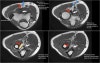

연속적인 관상면 영상에서 UCL을 볼 수 있습니다.

정상적인 UCL이 sublime tubercle에 확실하게 붙어 있는 것을 볼 수 있습니다.

Proximal part에서 약간의 high signal이 보이는 것은 정상입니다(arrow).